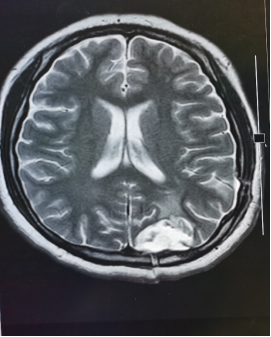

结核性脑膜脑炎患者。

颅内多发病灶、高颅压、脑肿胀、脑室受压,导致意识障碍。